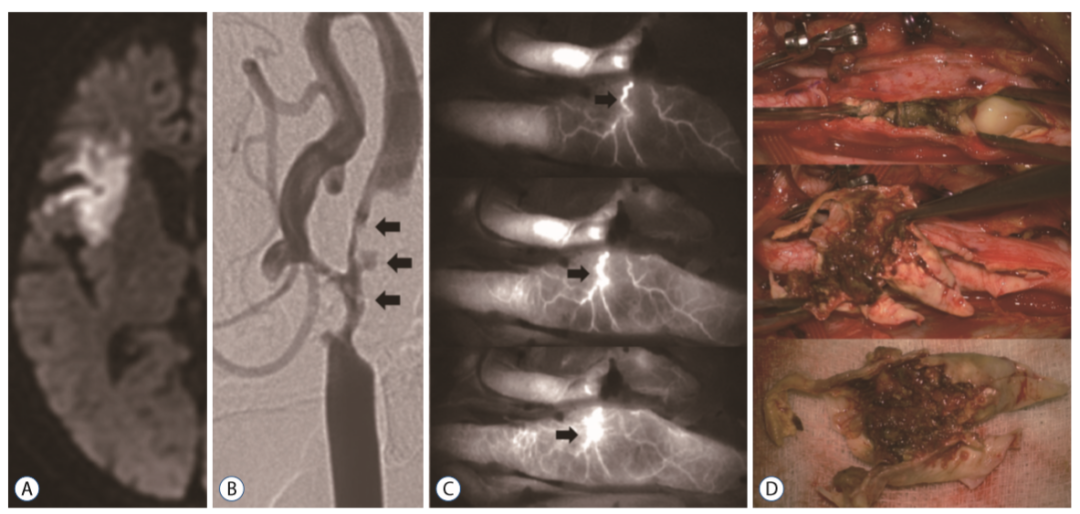

吲哚菁绿视频血管造影(Indocyaninegreen video angiography,ICG-VA)通常用于颅内动脉瘤手术、搭桥手术和颈动脉内膜切除术(CEA)中,以确定血管通畅程度并实时观察损伤状态。在本实验中,ICG-VA主要用于确定滋养血管类型。

外源血管滋养管(Vasa vasorum externae,VVE),源自于动脉分支,之后再回来供养同一血管。

自2015年9月至2017年12月,纳入69例行CEA的患者(症状性患者,狭窄程度≥50%;无症状患者,狭窄程度≥70%)。CEA期间,在切开颈动脉之前,由一名麻醉师在进行血管造影时静脉注射ICG,分析造影结果,确定管腔狭窄情况以及滋养血管类型。

所有患者均观察到了滋养血管,其中外源血管滋养管(VVE)11例(16%),内源血管滋养管(VVI)57例。VVE型与颈动脉易损斑块(90.9%,p = 0.017)密切相关。与稳定斑块相比,不稳定斑块中观察到CD68染色的巨噬细胞和CD117染色的肥大细胞的频率更高。